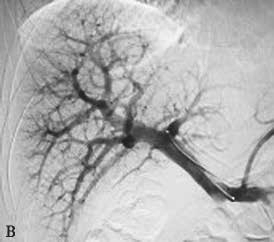

PVE栓塞材料多样,包括弹簧微钢圈、明胶微球、吸收性明胶海绵、凝血酶、超乳化碘油、纤维蛋白胶、无水乙醇、聚乙烯醇颗粒、氰基丙烯酸正丁酯(N-Butyl cyanoacrylate,NBCA)等,多种材料个体化联合应用能够增强栓塞效果(图2-5-1)。

图2-5-1 采用不同栓塞材料实施PVE

A、a.弹簧微钢圈栓塞门静脉右支;

B、b.氰基丙烯酸正丁酯栓塞门静脉右支和Ⅳ段支;

C、c.微钢圈联合氰基丙烯酸正丁酯栓塞门静脉右支。